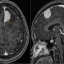

Triệu chứng quen thuộc hé lộ hội chứng mạch máu hiếm gặpTới cơ sở y tế thăm khám vì những triệu chứng tưởng chừng rất phổ biến như đau đầu, chóng mặt, nhìn mờ, một nữ bệnh nhân trẻ tuổi tại Hà Nội đã được các bác sỹ phát hiện mắc hội chứng Sturge-Weber. Đây là rối loạn bẩm sinh liên quan đến bất thường mạch máu cực kỳ hiếm gặp. -